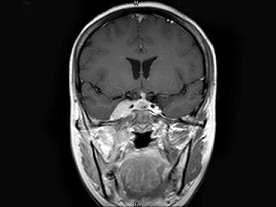

女,34岁。右侧听力下降,耳鸣2个月。MRI平扫及增强扫描如图示,最可能的诊断是 ( ) EBH-00871.jpg EBH-00872.jpg EBH-00873.jpg EBH-00874.jpg

• D.神经源性肿瘤